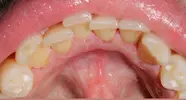

Dental Caries

Dental and Gum Diseases

Implant Treatment